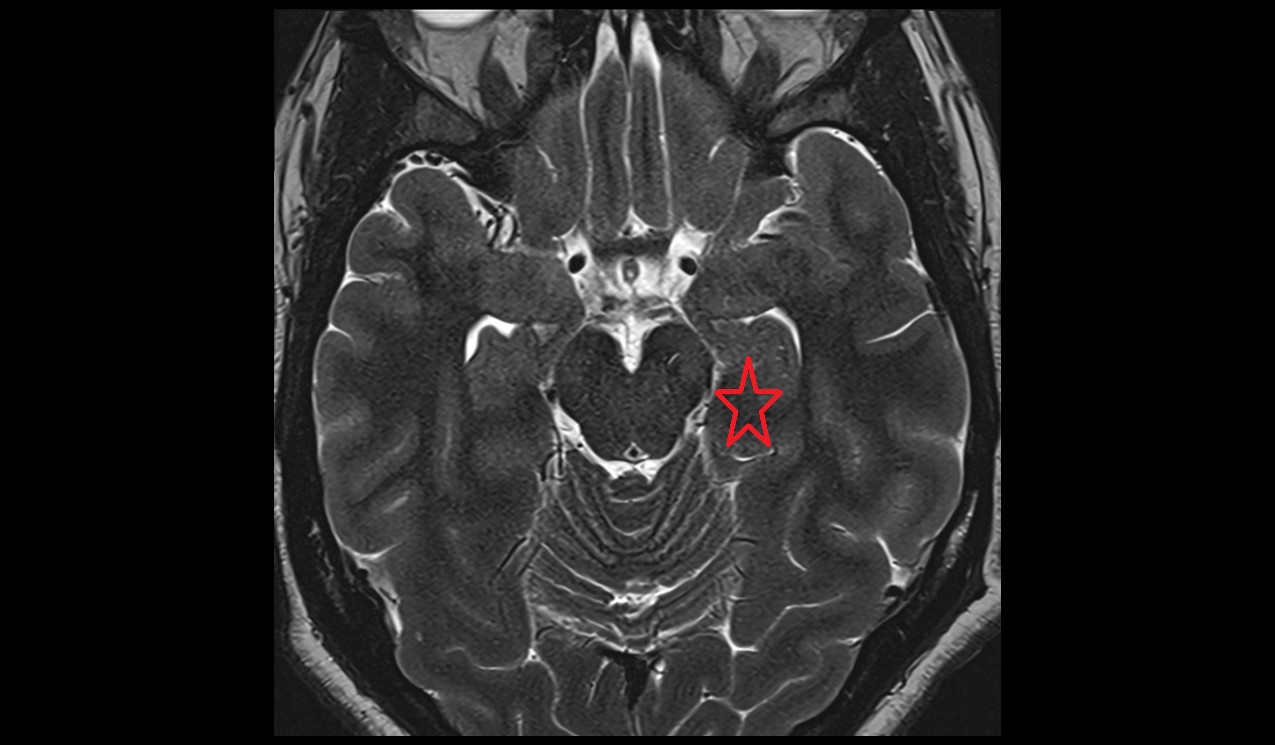

- Crural cistern

- Posterior cerebral artery (P2 Segment)